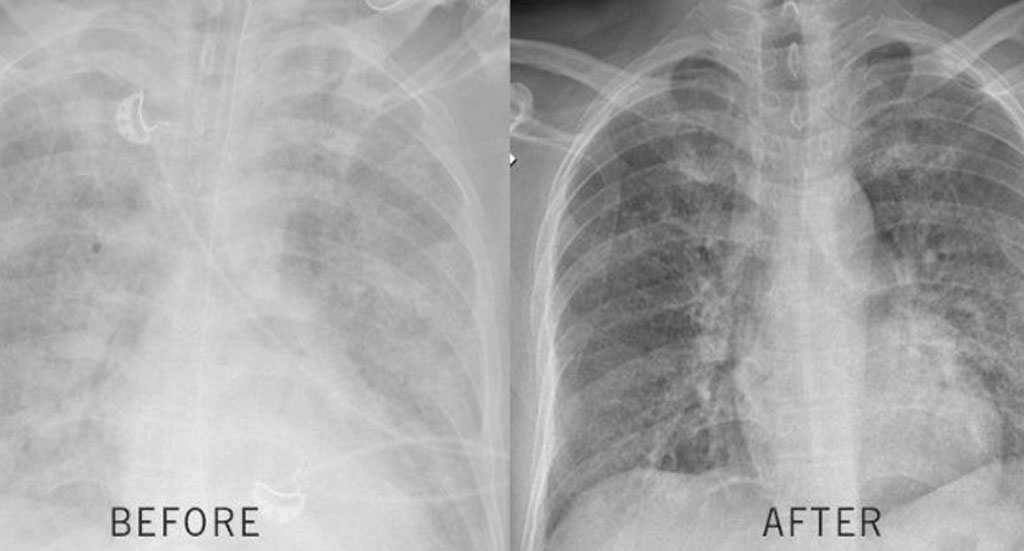

A few months ago my COPD symptoms were really limiting my daily life. Climbing stairs or carrying groceries would leave me struggling to catch my breath. My doctor ordered a chest X-ray, and when he showed it to me, the areas of congestion and reduced airflow were pretty obvious. Fortunately, tha'ts when I started following the routine and stuck with it every day. I chose the full 6 month treatment, but just after 7 weeks, I noticed my chest didn’t feel as heavy and I could take fuller breaths. At my next checkup, another X-ray was taken. My doctor said my lungs appeared less congested than before and my breathing capacity seemed improved during testing.

A few months ago my COPD had gotten so bad I could barely climb the stairs without stopping. My doctor showed me my lung X-ray and said my lungs looked pretty congested. It honestly scared me. I ordered the 4 bottle discounted offer and started doing the breathing method from the video every day. A few weeks later I went back for another checkup and when my doctor was shocked when he saw the new X-ray. My lungs looked much clearer, and I could really feel the difference in how much easier it is to breathe now.